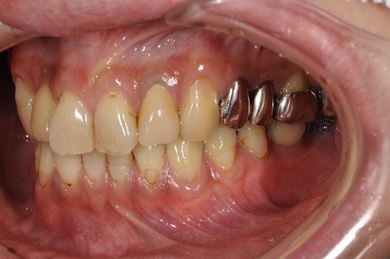

| 性別/年齢 | 男性 / 36歳 | ||||||||||||||||||||||||||||||||

| 主訴 | 義歯・インプラントの相談。 | ||||||||||||||||||||||||||||||||

| 治療方針 | 抜歯と同時にインプラント埋入を行い、治療期間を短縮する。 | ||||||||||||||||||||||||||||||||

| 治療内容 | インプラント4本(抜歯即日スピードインプラント)、メタルボンドセラミッククラウン4本 | ||||||||||||||||||||||||||||||||